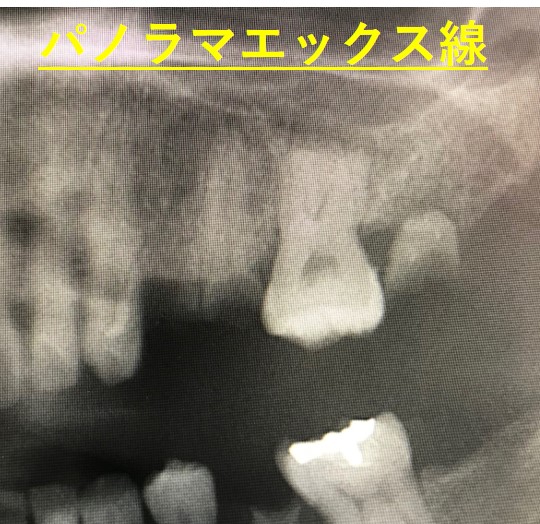

パノラマエックス線写真では、上の真ん中に膿の袋が見えます。しかしながら、2本の歯根が重なっていてどちらの膿かわかりません。

このパノラマエックス線写真をわかりやすく見てみると、赤〇が膿の袋で、④(オレンジ)と⑤(青)の歯根が重なっています。赤〇の膿は一体どちらの膿なのでしょうか。